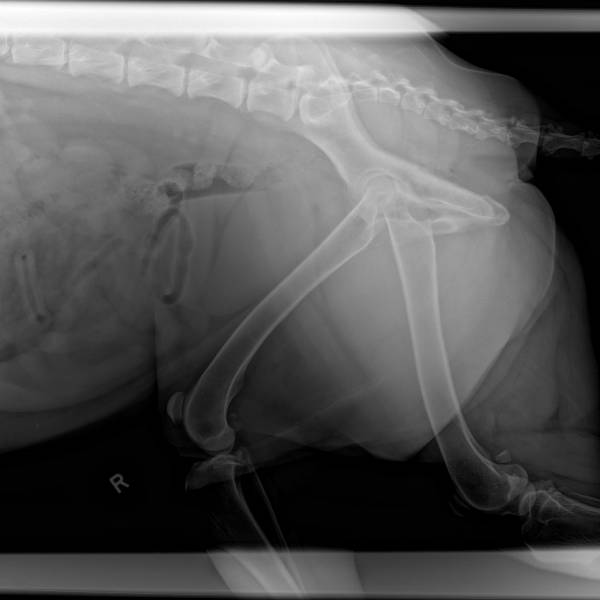

This is my 4 year old GSD.

I welcome any comments on his XRays.

Did you send these in to OFA or the SV? I hope not as the dog is not positioned correctly in the hip xrays. I would have them re-done at a vet that is skilled and knows how to CORRECTLY position a dog for hip xrays.

As for the Patellas.... I do not have enough experience with those. So I will not comment on them.

Right hip looks slightly loose but really not so bad for his age; I think both hips are at least fair; cannot comment on knees. Probably wanted to see if noise was coming from knees. Best of luck Nan

The vet is said at some point he may need a hip replacement.

IMO this dog would receive OFA clearance. I see absolutely nothing wrong with his hips. A hip replacement in the future? My concern would be with finding me a new vet ![]()